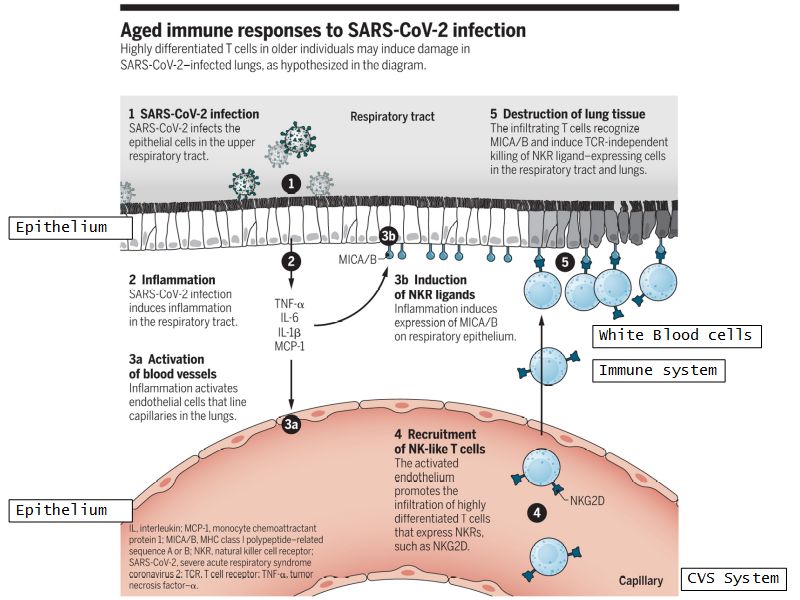

- Clinical application

- VERY topical example

- Aging immunity may exacerbate COVID-19

- Arne N. Akbar, Derek W. Gilroy

- Science 17 Jul 2020:

- Vol. 369, Issue 6501, pp. 256-257

- DOI: 10.1126/science.abb0762